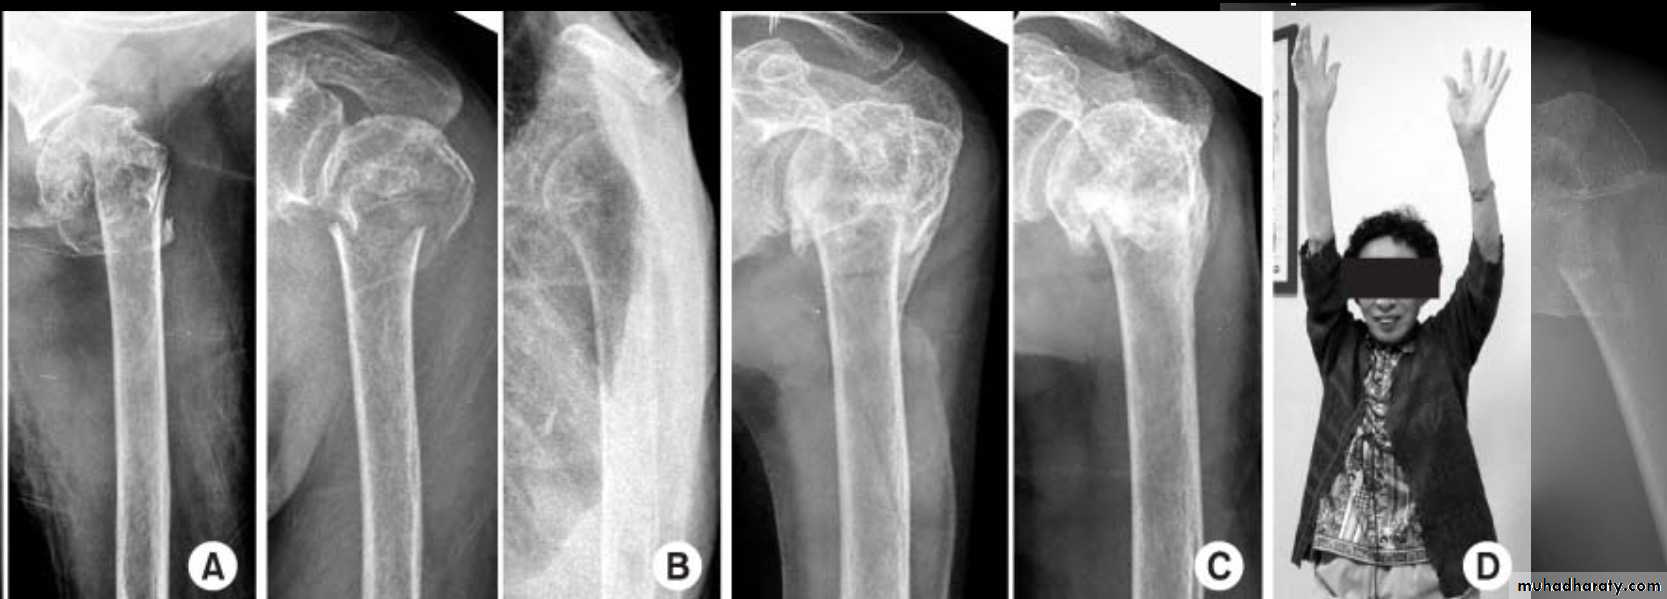

X RAY

27

28

CT

29

TREATMENT

30

ORIF